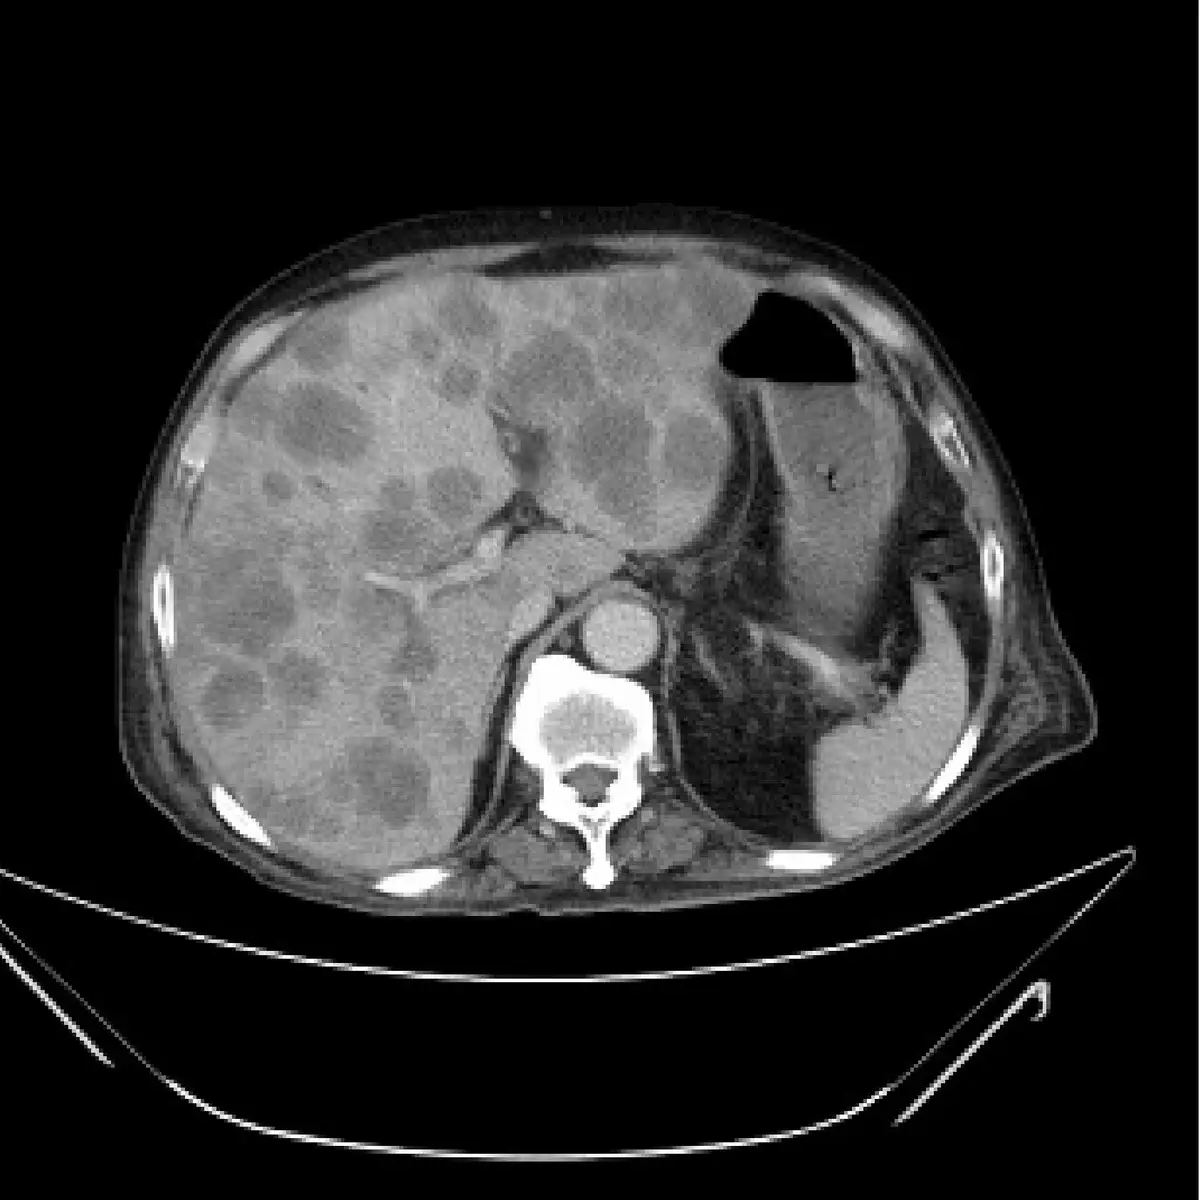

下圖 為腹部電腦斷層攝影影像,最可能的診斷為下列何者?

本題考核腹部電腦斷層攝影(computed tomography, CT)中肝臟多發性病灶的影像判讀能力。核心重點在於:肝臟轉移癌(hepatic metastases)在 CT 上呈現的多發性低密度病灶,與肝硬化再生結節、肝出血、脂肪肝的影像特徵鑑別。

本題 CT 影像為腹部橫切面(axial view),以門靜脈期(portal venous phase)或對比增強後呈現。影像所見:

- 肝臟(右側大區域):肝臟體積正常至略大,整體輪廓規則,無結節狀外觀(排除肝硬化可能)。肝實質內可見多發性、大小不一的圓形/橢圓形低密度(hypodense)病灶,散布於全肝各葉,數量達 10 個以上,部分病灶邊緣可見輕微環狀強化(ring enhancement),呈現典型「瑞士乳酪」(Swiss cheese pattern)外觀。

- 肝臟密度:整體肝實質密度正常(無瀰漫性密度降低,可排除脂肪肝);無高密度區域(排除急性出血)。

- 脾臟、腎臟:體積外觀正常,無腹水,無肝門靜脈高壓徵象。

影像判讀結論:多發性低密度病灶散布全肝,邊緣有環狀強化,最符合肝臟轉移癌影像特徵。